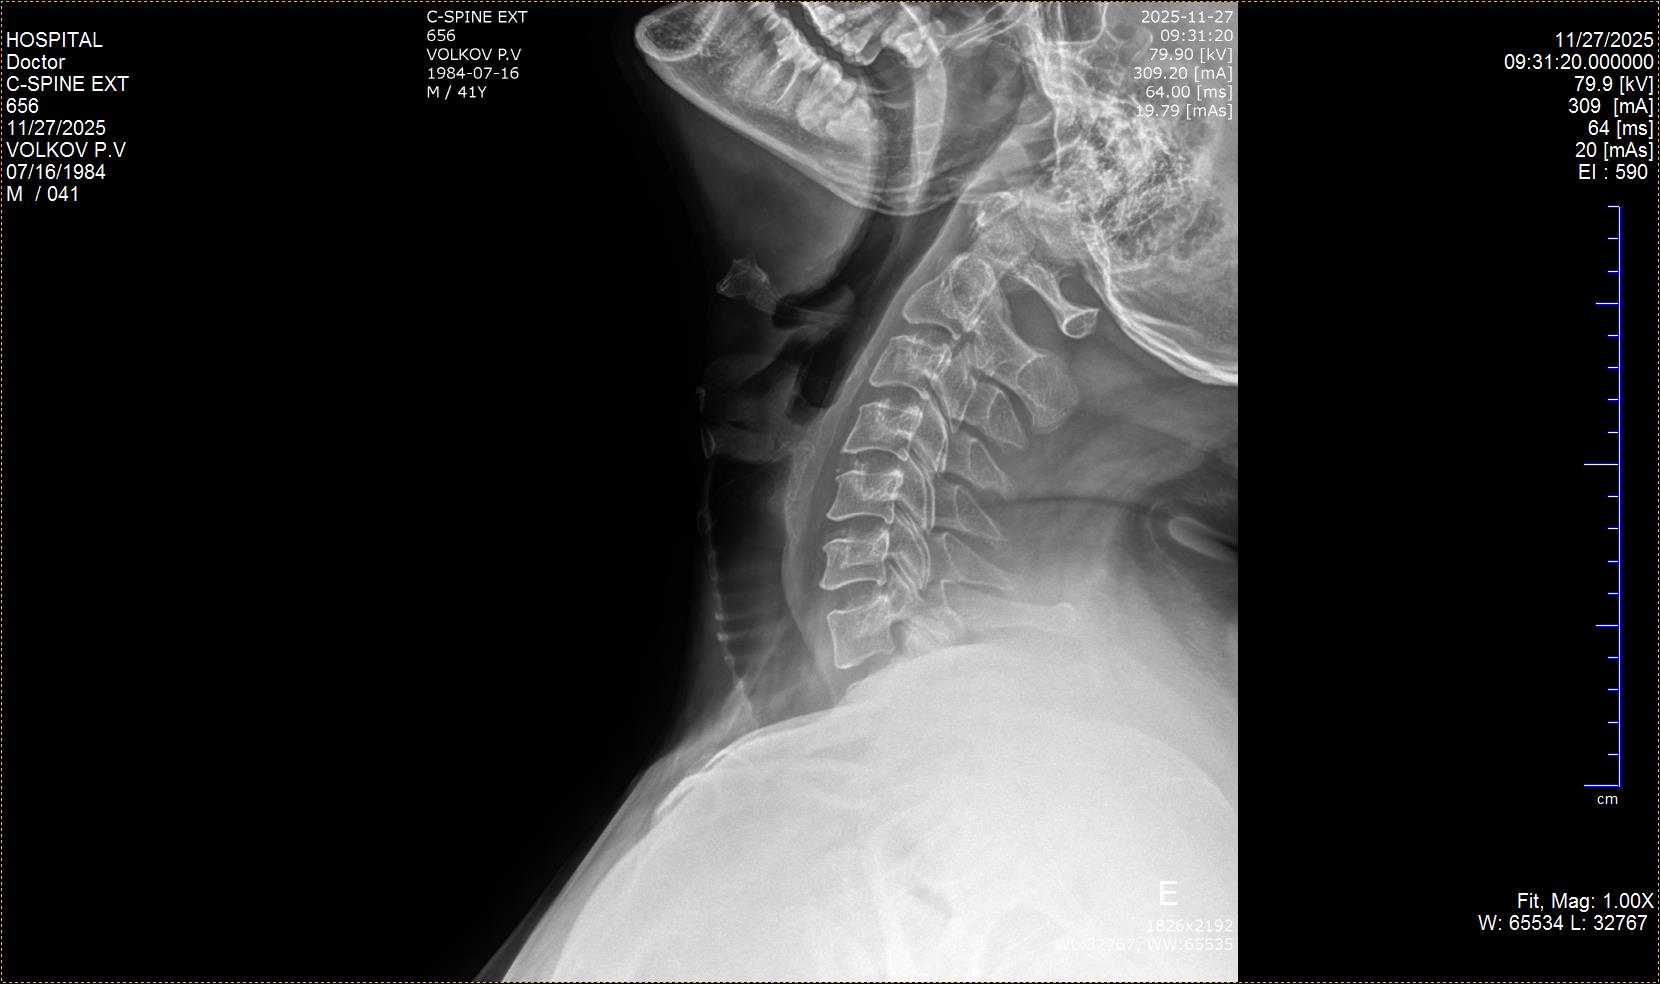

Помогите, пожалуйста, расшифровать снимки.  Не поворачивается голова вправо, при попытке  через силу мышцами её повернуть начинается боль слева и в затылочной части. Один врач  ставит остеохондроз, спондилоартроз. Второй просто остеохондроз и сколиоз 1 степени.  Третий: остеохондроз 2ст., спондилоартроз 1ст.

Одной из причин боли и ограничения движений у Вас может быть шилоподъязычный синдром. У Вас удлинённые шиловидные отростки. Для подтверждения/исключения потребуются консультации челюстно-лицевого хирурга, лор-врача и невроолога.